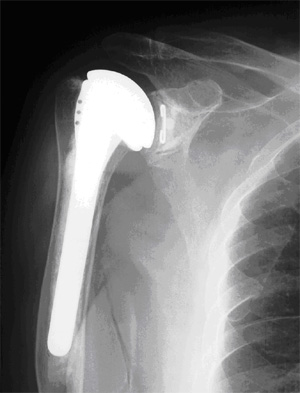

人工肩関節置換術の例

人工関節には股関節、膝関節、肩関節、肘関節などがありますが、股関節と膝関節の人工関節置換術は非常に推奨される手術といわれています。肘関節、肩関節の人工関節置換術は普通に推奨されるというレベルです。

人工関節に関して、当院では股関節、膝関節、肩関節、肘関節を行っています。特に多いのは股関節、膝関節です。年間、人工関節手術を130例くらいやっていますが、股関節・膝関節で120例、肩、肘が10例程度というところです。

肘や肩関節に関しては、体重のかかる関節ではありませんから、歩行には問題ありませんが、食事や排泄、衣服の着脱など日常生活を送る上で非常に重要であり、リウマチの場合は手、肘、肩関節が破壊されると日常生活が非常に困ります。ですから、すべての関節ではなくても、一部の関節を人工関節にするのも非常に有効と思います。